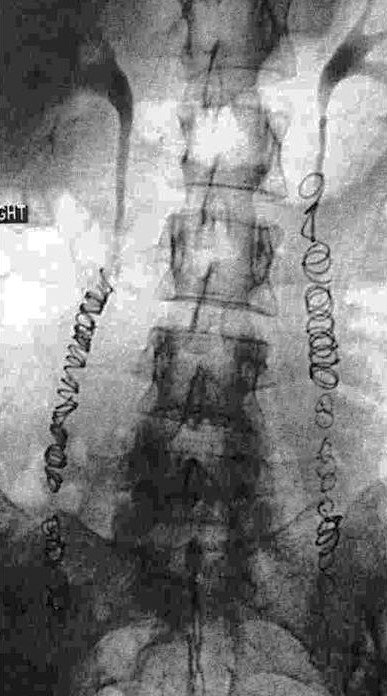

Примечательно, что абсолютно верную и точную информацию о наличии заболевания, состоянии вен малого таза на финальном этапе обследования помогает получить проведение инвазивного рентгеноконтрастного исследования. Во время селективной оварикографии и тазовой флебографии врачи уточняют анатомические особенности положения, строения яичниковых сосудов, их диаметр, выявляют количество и характер притоков гонадных сосудов, наличие рефлюкса, свойственного внутренним и яичниковым подвздошным венам, а также связь подкожных и сосудов малого таза.

Данная процедура предусматривает введение эмболизационных (закупоривающих) спиралей в вену через диагностический катетер, что позволяет полностью закупорить патологический кровоток. Операция не занимает много времени. При этом пациент может вернуться к привычной жизни уже в ближайшее время. Период реабилитации является несложным.